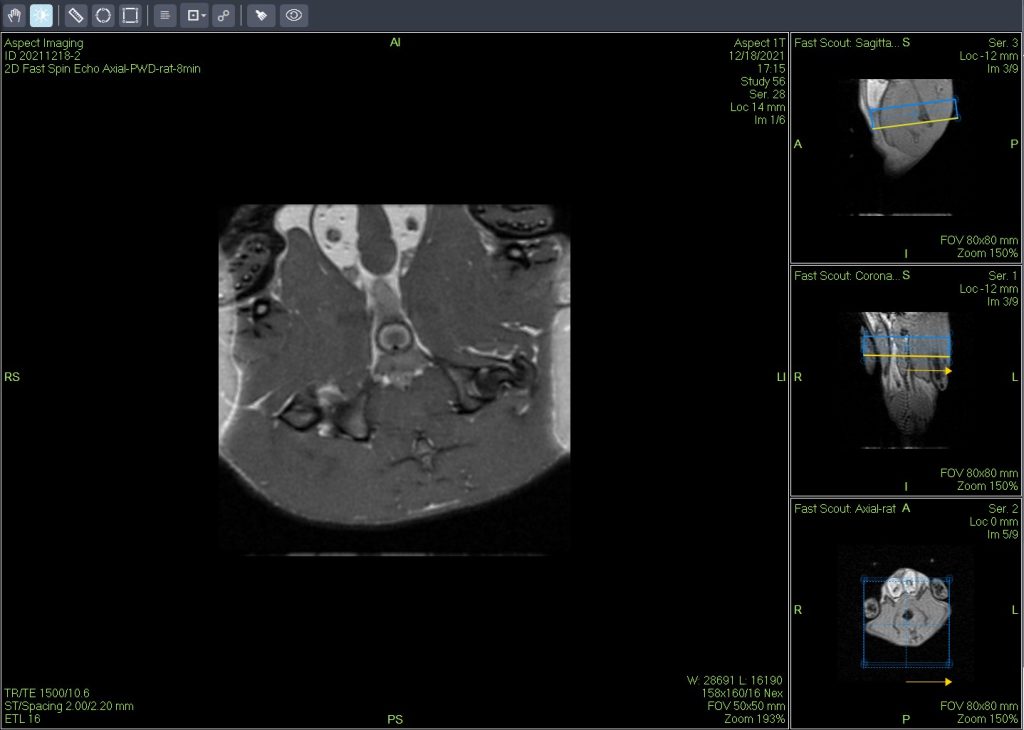

In vivo MRI detected focal liver injury in a mouse model (Fig. A). High-resolution ex vivo MRH identified several distinct focal fatty lesions in the liver (Fig. B and C). Routine histopathology confirmed these lesions as focal fatty changes (Fig. C).